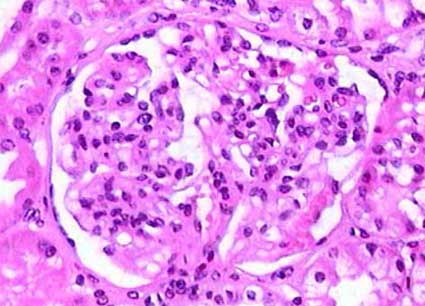

For more than 50 years, it has been known that C3 is deposited in over 90% of IgA nephropathy cases. The trial findings point to complement activation as one of the key drivers behind the condition’s progression. However, as promising as these findings are, they also remind us that managing the disease is layered with tricky parts, tangled issues, and some rather complicated pieces that demand a deeper look.

One of the main takeaways from the trial is that complement activation does not occur uniformly among all patients with IgA nephropathy. Despite the general observation of C3 deposition, the intensity and nature of complement activation can vary considerably. This disparity hints at several biological twists and turns that make it tough to design a one-size-fits-all treatment regimen.

It is critical to remember that IgA nephropathy is not a uniform condition. Even though the majority of patients share the common sign of C3 deposition, the intensity and the timing of complement activation can differ. This means that while iptacopan may be a promising therapy, it might not be the ideal solution for everyone.

| Degree of Complement Activation | The level of C3 deposition may influence the therapeutic response to iptacopan. |